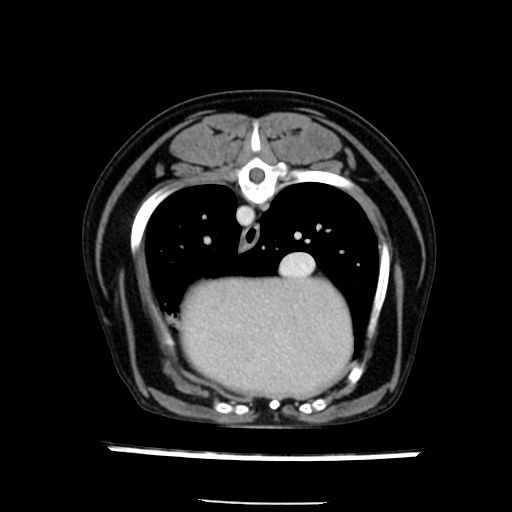

prescritto esame TAC

sequenza immagini limitata al fegato reni e surreni

le immagini ecografiche rispetto alla tac datano circa 7 mesi prima ,le surrenali sono normali nonostante il test acth sia risultato positivo .all’esame TAC dopo diversi mesi risultano aumentate armonicamente nel volume e si individua un forte sospetto di adenoma ipofisario .

sospetto adenoma ipofisario vs. meno probabilmente meningioma della base; intertiziopatia polmonare; lesione espansiva epatica, verosimilmente del lobo laterale sinistro, di sospetta natura neoplastica; lesioni spleniche di natura da definire; iperplasia/ipertrofia delle ghiandole surrenali, bilateralmente; vertebra di transizione del rachide toracico; tenosinovite cronica del muscolo bicipite brachiale di destra.

la tac dopo 7 mesi permette misure tridimensionali 5,2 x 9,2 x 4,5 cm (forma piu’ allungata )